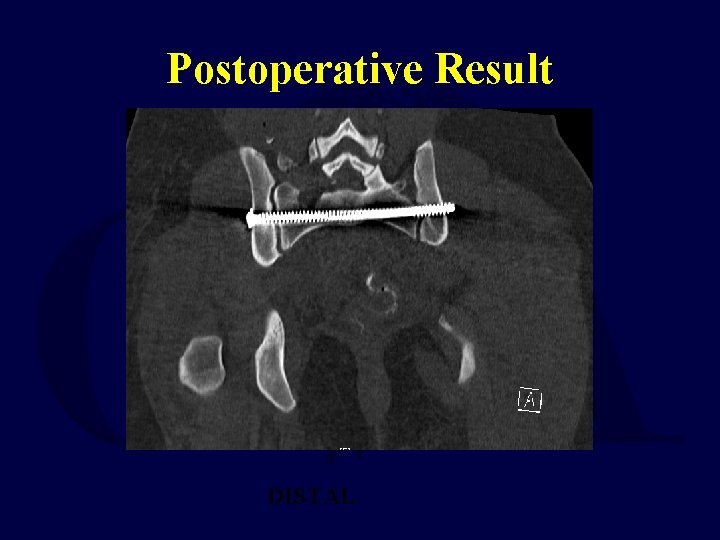

Postoperative Result DISTAL